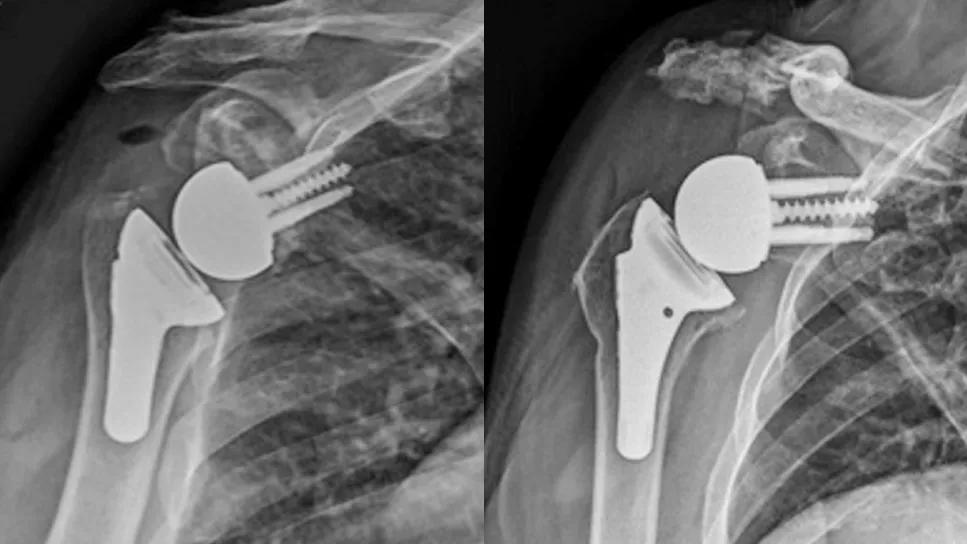

X-rays of total shoulder replacement

X-rays of 3 total shoulder replacements

Preoperative (top) and postoperative (bottom) X-rays of: a patient with glenohumeral osteoarthritis who underwent rTSA (A), a patient with rotator cuff tear arthropathy who underwent rTSA (B), and a patient with glenohumeral osteoarthritis who underwent anatomic TSA (C).